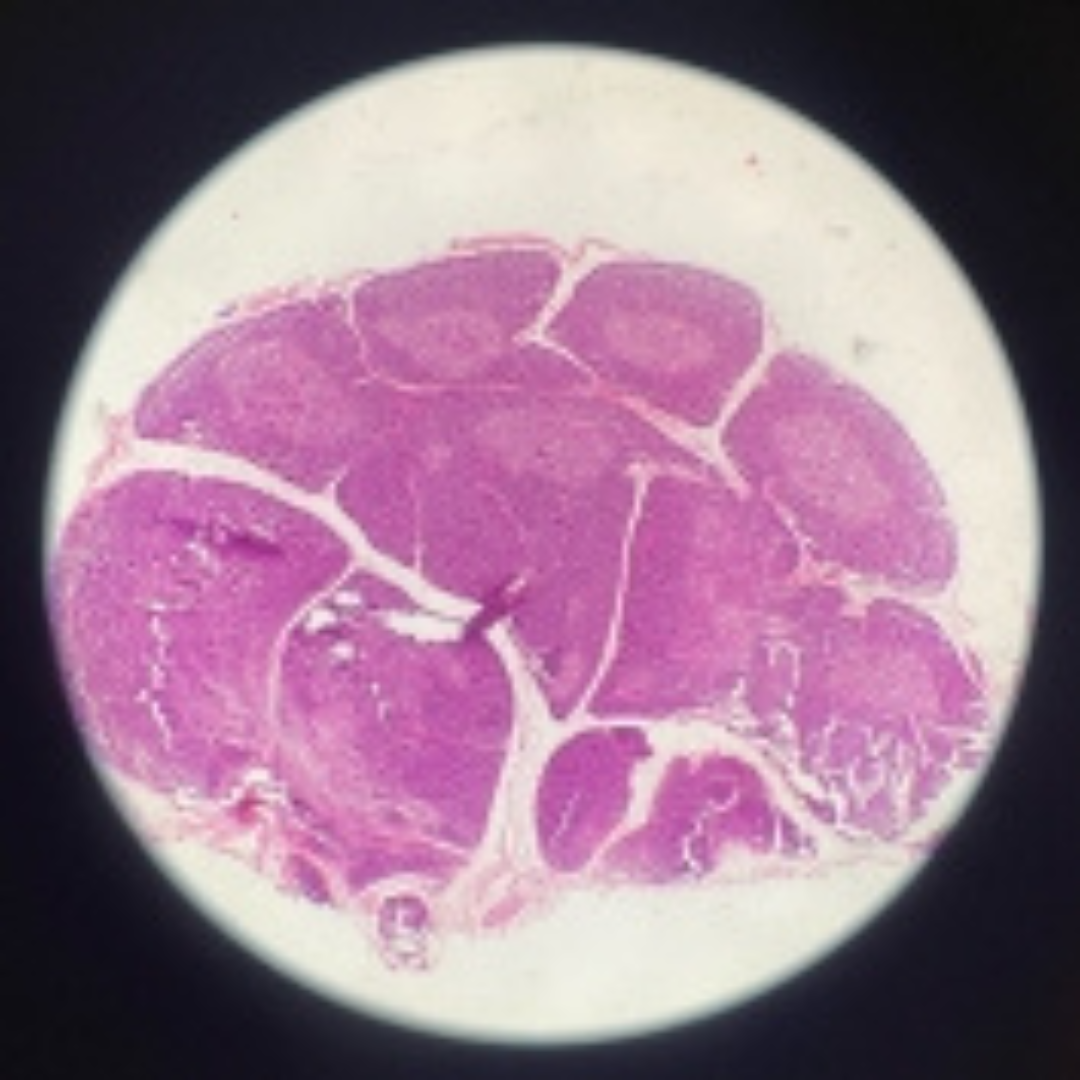

Spleen

21

New cards

Spleen

22

New cards

Spleen

23

New cards

Spleen

24

New cards

Spleen

25

New cards

Spleen

26

New cards

Spleen

27

New cards

Spleen